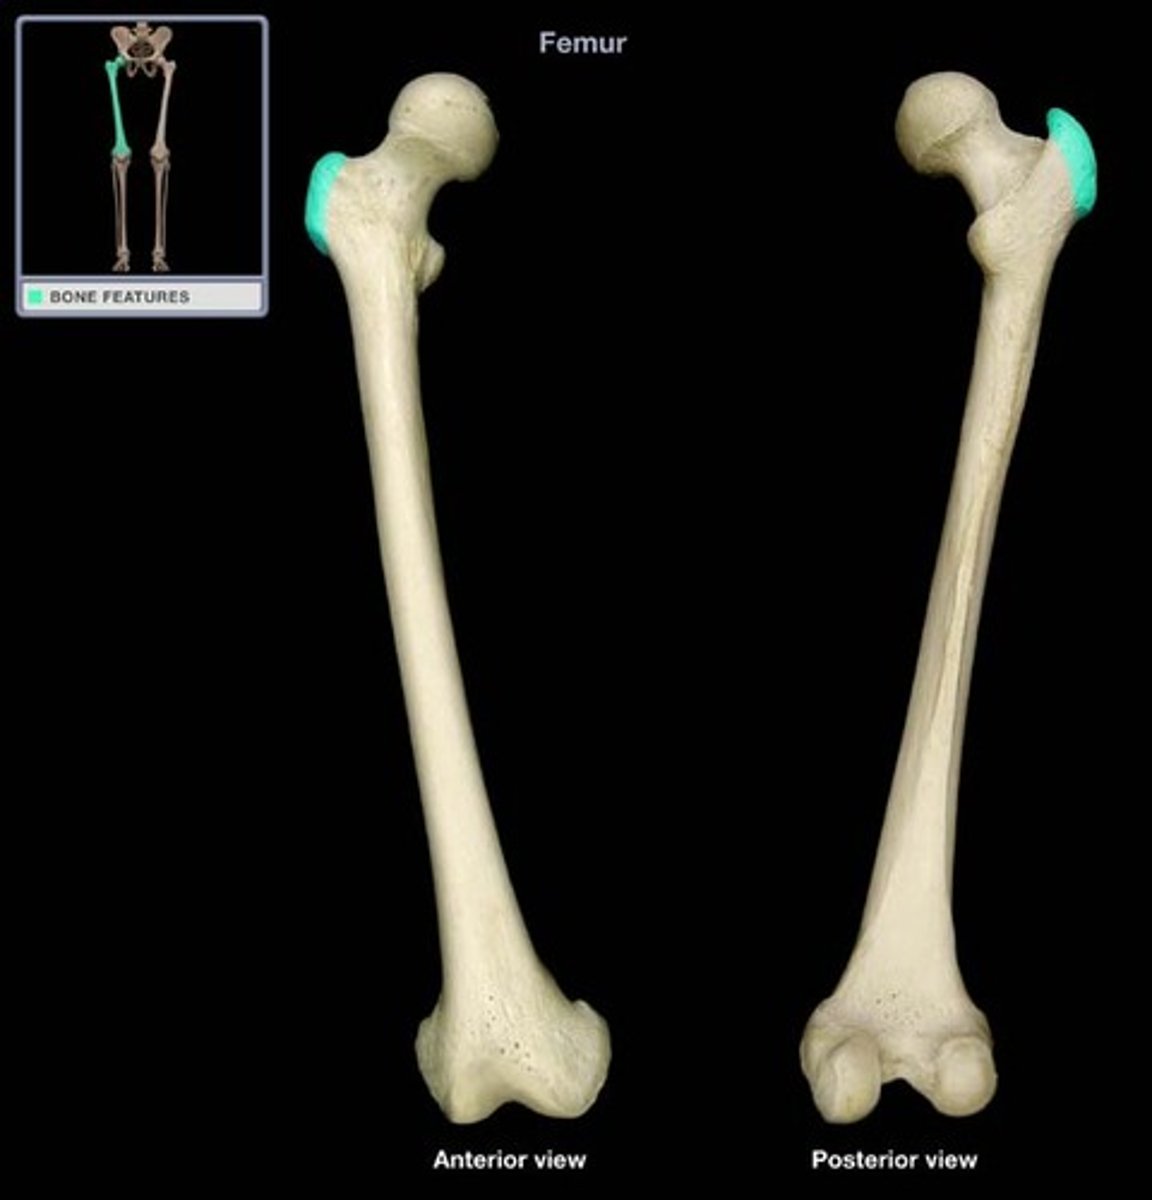

Femur

Greater Trochanter